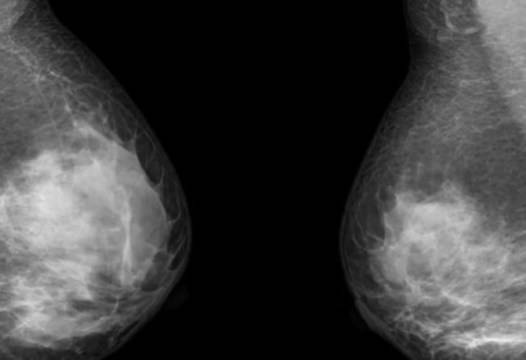

Препоръчва се всеки месец да проверявате гърдите си за всякакви промени. Факт е, че около 40% от жените с рак на гърдата са открили тумор.

И не става въпрос само за наличието на неоплазми. Внимание трябва да се обърне и към промяната на кожата на зърното, на секрет от зърното, особено ако това се случи само от едната страна. Другите симптоми включват промяна във формата на гърдата, която не е свързана с менструалния цикъл, бременността или кърменето; прибрана или сплескана; вдлъбнатина в гърдите, която не изчезва след свалянето на сутиена; постоянна болка от едната страна; кожа, която бързо променя цвета; бучка в подмишницата.